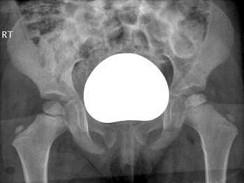

女,4岁,左腿跛行2个月。结合图像,最可能的诊断是?(?)A.骨囊肿B.软骨肉瘤C.骨肉瘤D.髋关节结核E.股骨头骨骺缺血坏死

问题 女,4岁,左腿跛行2个月。结合图像,最可能的诊断是?(?)

选项 A.骨囊肿 B.软骨肉瘤 C.骨肉瘤 D.髋关节结核 E.股骨头骨骺缺血坏死

答案 E